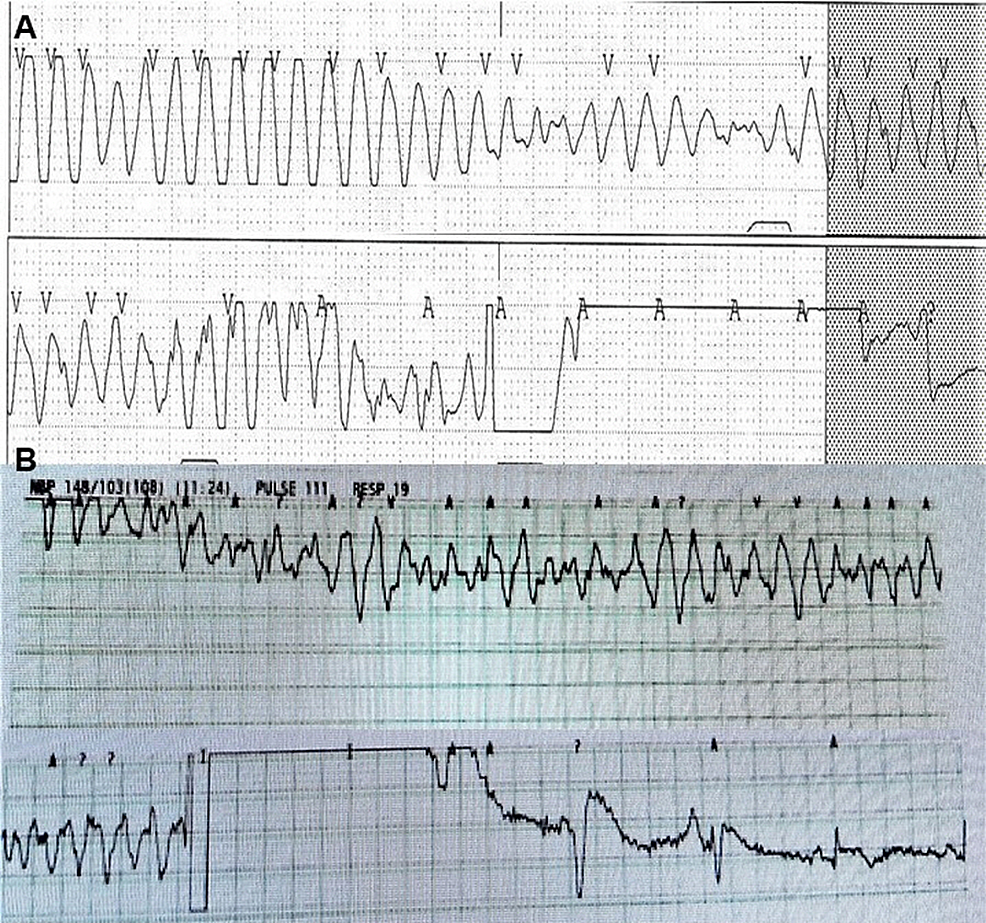

From www.cureus.com

Cureus Ventricular Arrhythmia Associated With Magnesium and Vitamin D Vitamin D Deficiency Heart Arrhythmia Vitamin d deficiency has been linked with hypertension, coronary artery disease, and stroke, but there is no consensus regarding the. Atrial fibrillation is a common cardiac arrhythmia with high morbidity risk. Vitamin d deficiency is associated with cvd including cardiac fibrosis. A significant number of studies have correlated vitamin d deficiency with an increased risk of developing cardiac arrhythmias and. Vitamin D Deficiency Heart Arrhythmia.

Cureus Ventricular Arrhythmia Associated With Magnesium and Vitamin D Vitamin D Deficiency Heart Arrhythmia A significant number of studies have correlated vitamin d deficiency with an increased risk of developing cardiac arrhythmias and sudden. Observational studies suggest that vitamin d deficiency is associated. A significant number of studies have correlated vitamin d deficiency with an increased risk of developing cardiac. Atrial fibrillation is a common cardiac arrhythmia with high morbidity risk. Vitamin d deficiency. Vitamin D Deficiency Heart Arrhythmia.

Cureus Ventricular Arrhythmia Associated With Magnesium and Vitamin D Vitamin D Deficiency Heart Arrhythmia Vitamin d deficiency has been linked with hypertension, coronary artery disease, and stroke, but there is no consensus regarding the. A significant number of studies have correlated vitamin d deficiency with an increased risk of developing cardiac. A significant number of studies have correlated vitamin d deficiency with an increased risk of developing cardiac arrhythmias and sudden. Observational studies suggest. Vitamin D Deficiency Heart Arrhythmia.

Cureus Ventricular Arrhythmia Associated With Magnesium and Vitamin D Vitamin D Deficiency Heart Arrhythmia Observational studies suggest that vitamin d deficiency is associated. Although vitamin d deficiency is undoubtedly bad for cardiovascular health, there is also some evidence that high. A significant number of studies have correlated vitamin d deficiency with an increased risk of developing cardiac arrhythmias and sudden. Vitamin d deficiency has been linked with hypertension, coronary artery disease, and stroke, but. Vitamin D Deficiency Heart Arrhythmia.